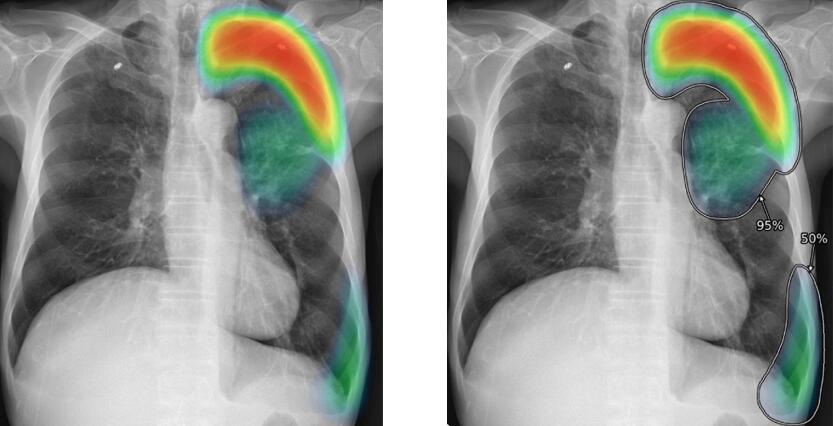

Anomaly detection in MRI images

It is designed to detect anomalies in medical imaging with high precision.

Using a powerful ensemble of state-of-the-art segmentation and classification deep-learning models, the system analyzes MRI scans to identify structural abnormalities across various organs.

The solution produces pixel-level segmentation masks, highlights regions of concern, and classifies detected anomalies—helping radiologists accelerate diagnosis, reduce oversight errors, and improve clinical decision-making.